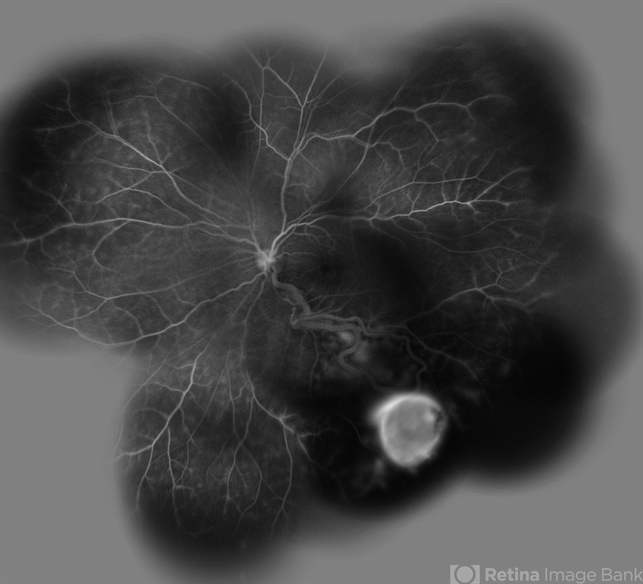

- Von Hippel-Lindau

- Wide filed late phase FA image of the left eye of a 30-year-old woman with Von Hippel Lindau.